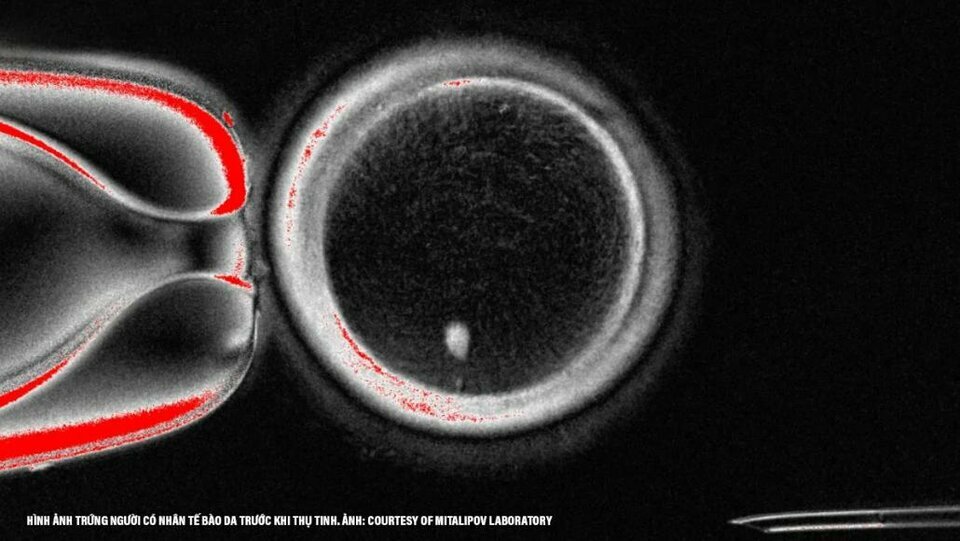

Cụ thể, các nhà khoa học đã lấy nhân (chứa bộ DNA hoàn chỉnh) từ một tế bào da của người, sau đó cấy nó vào "vỏ" của một tế bào trứng đã được loại bỏ nhân. Tuy nhiên, thay vì tạo ra một bản sao y hệt, mục tiêu của họ là "ép" tế bào mới này phải trải qua một quá trình giảm phân, loại bỏ đi một nửa số nhiễm sắc thể để nó có thể sẵn sàng kết hợp với một tinh trùng trong quá trình thụ tinh.

Cụ thể, các nhà khoa học đã lấy nhân (chứa bộ DNA hoàn chỉnh) từ một tế bào da của người, sau đó cấy nó vào "vỏ" của một tế bào trứng đã được loại bỏ nhân. Tuy nhiên, thay vì tạo ra một bản sao y hệt, mục tiêu của họ là "ép" tế bào mới này phải trải qua một quá trình giảm phân, loại bỏ đi một nửa số nhiễm sắc thể để nó có thể sẵn sàng kết hợp với một tinh trùng trong quá trình thụ tinh.